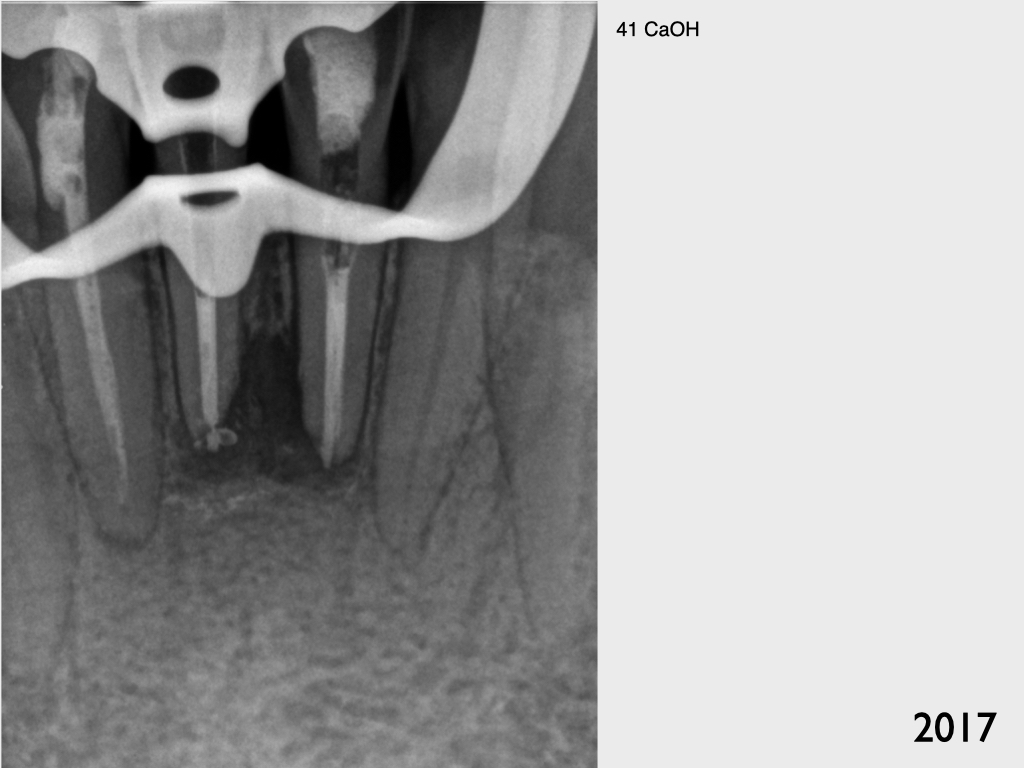

Frontzahntrauma